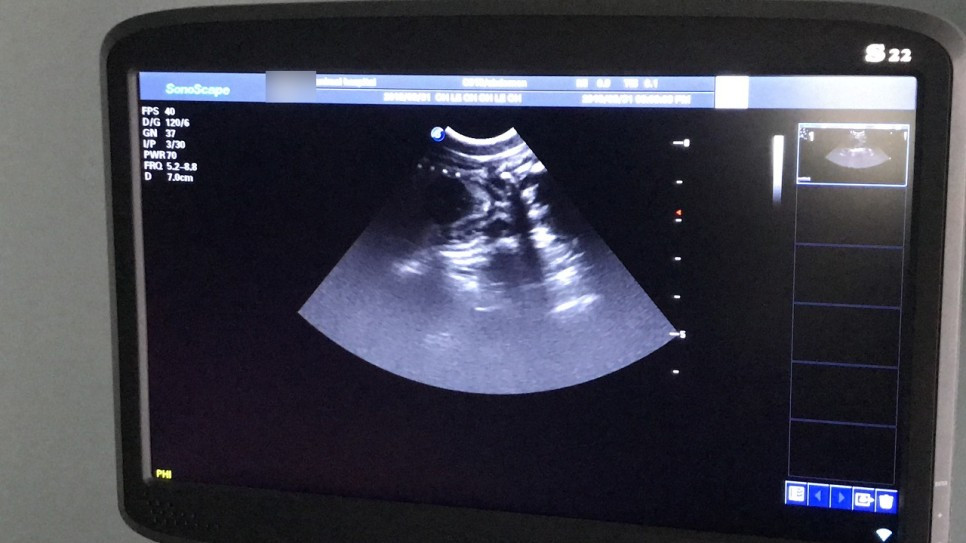

수의사 선생님과 면담을 했다. 우선은 초음파로 임신 여부를 확인해야 하는데, 임신 20일 이전의 초기 상태에서는 초음파로도 임신 여부가 확인되지 않는다고 한다. 하지만 친구에게 듣기론 레오의 배에 아기가 움직이는 게 육안상으로 보일 정도라고 했으니 초기는 아닐 것 같아 진행하기로 했다.

사나운 레오의 정신이 돌아왔으니 초음파를 진행하는 동안 화를 낼 거라고 생각했는데, 의외로 레오는 아주 얌전히 있어주었다. 정신만 돌아오고 기력은 돌아오지 않은 탓일까? 하지만 레오의 눈빛은 '이 인간들이 나를 도와주려는구나' 하고 이해하는 얼굴이었다.

초음파로 확인한 결과 레오는 임신이 맞았다. 아기 심장이 뛰는 것을 내 눈으로 직접 확인했다. 감격스럽고도 원망스러운, 대견하고도 안쓰러운 오묘한 감정이 들었다. 마릿수는 꽤 많아 보이는데, 정확한 마릿수는 초음파가 아닌 X-ray로 확인해야 한다고 한다. X-ray는 44,000원이었고 찍지 않았다. 가격 때문이 아니라 순간적으로 방사능이 걱정되어 한 선택이었는데, 집에 와서 '찍을걸, 찍어볼걸.'하고 매우 후회했다.